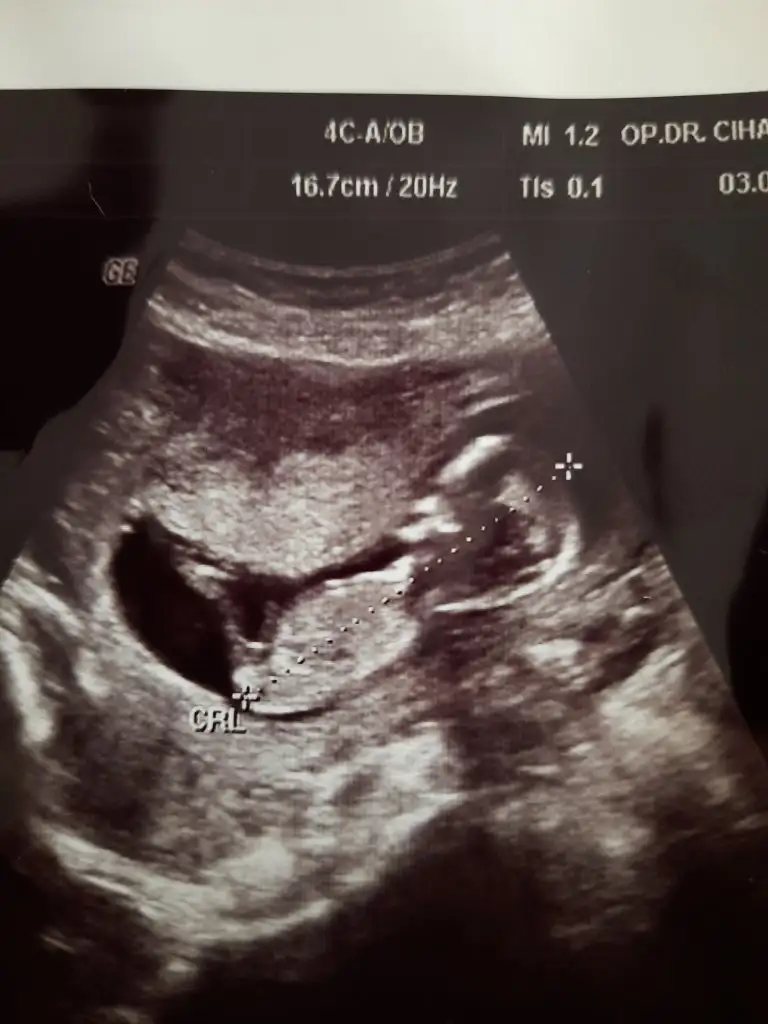

Erkek gibiSevgiliIkra meyra bu sefer ne görürsün acaba :) 12+1den görüntümüz :)

Erkek gibi sanki emin olamadım en iyi 11 12 13 haftalarEki Görüntüle 2896935 merhabalar tahmininizi alabilir miyim. SAT a göre 13+1 usg de 14 çıktı